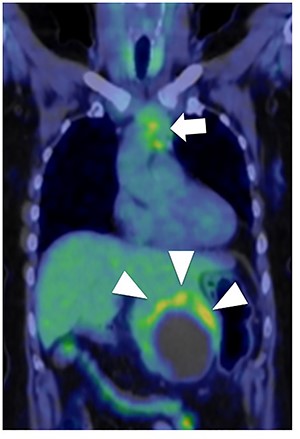

Fluorodeoxyglucose positron emission tomography. Maximum standard uptake value of the liver tumor (arrow head) was 4.8 and that of the anterior mediastinal tumor (arrow) was 3.9. Neither lymph node metastasis nor other distant metastasis was detected.